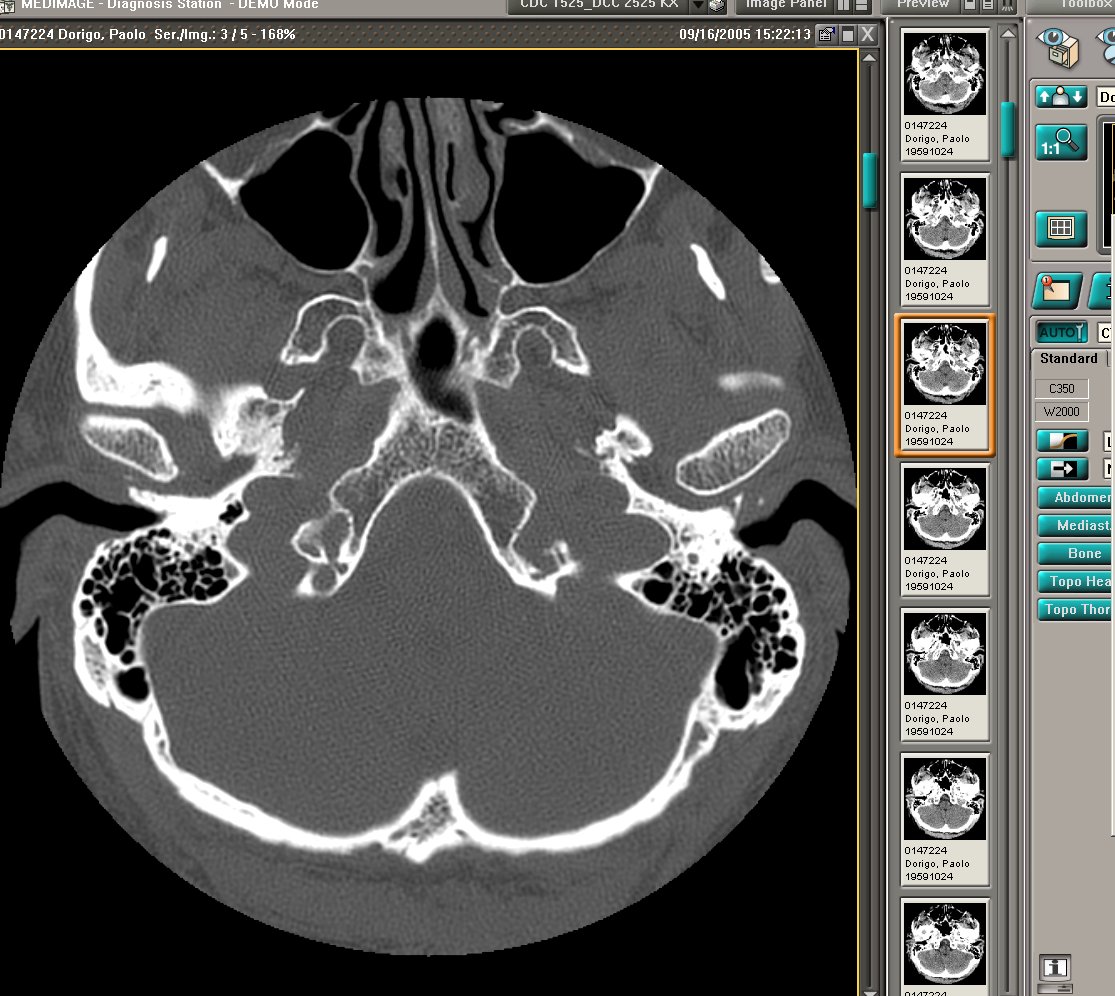

LA SCANSIONE TC RIPORTATA A PAG.32 (SOTTO) NON CORRISPONDE ANATOMICAMENTE ALLO ZIGOMO COME RIPORTATO MA AD UNA SEDE ANATOMICAMENTE CORRISPONDENTE ALL'OSTIO FARINGEO DX E SIN DELLA TUBA AUDITIVA. HANNO DENSITA' DI TIPO CALCIFICO ED ASPETTO "A CORONA DI PERLE"; NON SONO DI RISCONTRO USUALE. TRA LE IPOTESI "MEDICHE" SI POTREBBE IPOTIZZARE TRATTARSI DI PRECIPITATI CALCIFICI IN SEDE DI VECCHIO PROCESSO INFIAMMATORIO CHE TUTTAVIA NON RISULTA IN ANAMNESI.

IL REPERTO RELATIVO ALLE IMMAGINI DI PAG.29 ALL'ORECCHIO ESTERNO SIN.: LA MILLIMETRICA IMMAGINE NELLO SPESSORE DELLA PARETE ANTERIORE DEL CONDOTTO UDITIVO ESTERNO, DI RELATIVA IPERDENSITA' RISPETTO AI TESSUTI MOLLI ADIACENTI, NON HA CARATTERISTICHE DI CALCIFICAZIONE PARA-AURICOLARE, HA BASSA DENSITA', INFERIORE A QUELLA DEL CALCIO E PARAGONABILE A QUELLA CHE IN TC CORRISPONDE A CARTILAGINE.